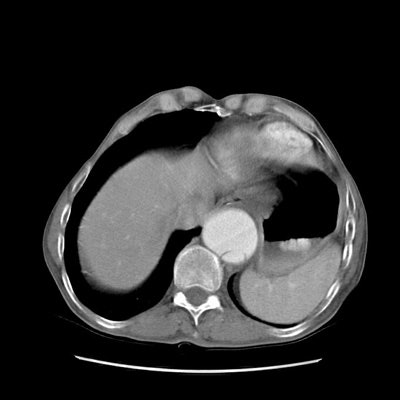

Type B dissection on CT:

The images below demonstrate a Type B aortic dissection beginning at the level of the thoracic outlet (note also aortic aneurysm). Both the superior mesenteric artery and the left renal artery arise from the false lumen. (Click images to enlarge)